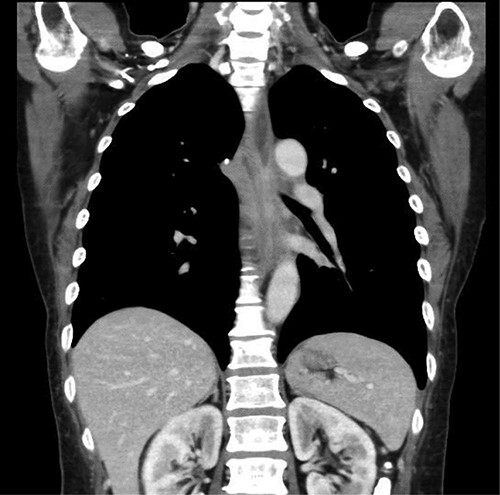

Preoperative computed tomography (CT) and barium meal studies were performed. The CT findings showed circumferential wall thickening with infiltrative change at the middle of the intrathoracic esophagus, with luminal dilation of the oral side of the stenotic esophagus (Figs 2, 3). The barium meal study showed no abnormal findings in the stomach (Fig. 4). Thoracoscopic esophagectomy was performed with the patient in the semi-prone position, followed by esophageal reconstruction using a gastric tube with the patient in the supine position. The operation was started with bilateral lung ventilation using a single-lumen endotracheal tube. A four-port thoracoscopic technique was used as follows: an observation port with a 10-mm scope was placed at the ninth intercostal space at the line of the inferior scapular angle, and two 5-mm ports and one 12-mm port for the intrathoracic procedures were placed at the third, fifth and seventh intercostal spaces, respectively, at the posterior axillary line (Fig. 5). Pneumothorax was created using 10 mmHg of CO2 to deflate the lung to achieve a better operative field. The pleura and connective tissue around the thoracic esophagus showed severe inflammatory and fibrotic changes. In particular, the middle thoracic esophagus was strongly adherent to the arch of the azygos vein and the tracheal bifurcation.

CT images showing a horizontal section of the esophagus; CT image shows circumferential wall thickening with infiltrative changes in the middle part of the thoracic esophagus.